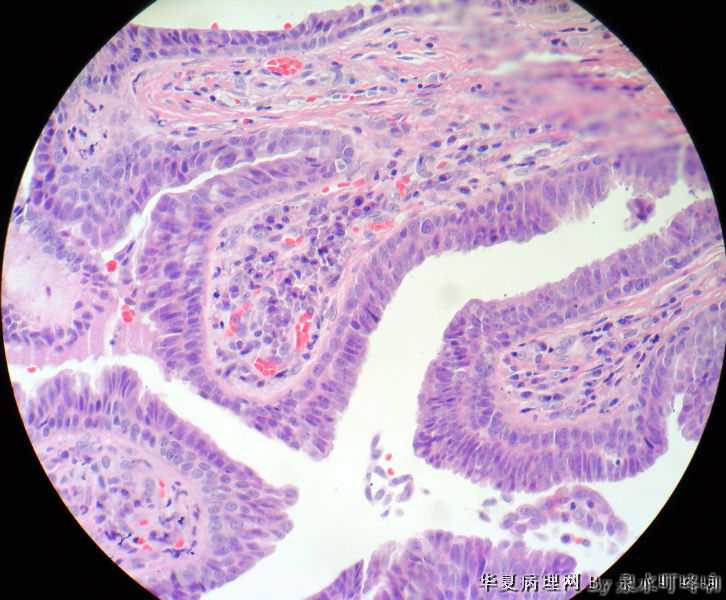

120175,男,63岁,左面部肿物半年。

大体:灰褐色肿物一个 ,大小约1.5×1.1×0.9厘米,切面灰褐色,质脆。

乳头状汗管囊腺瘤